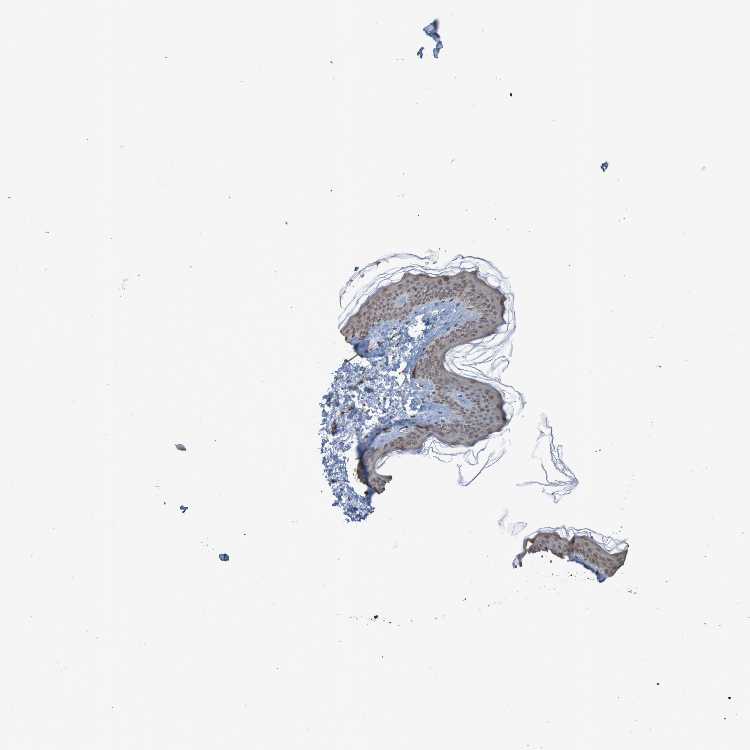

SKIN 1 - Antibody stainingi

Antibody staining in the annotated cell types in the current human tissue is reported as not detected, low, medium, or high, based on conventional immunohistochemistry profiling in selected tissues. This score is based on the combination of the staining intensity and fraction of stained cells.

Each image is clickable and will lead to virtual microscopy that enables deeper exploration of all samples and also displays staining intensity scores, fraction scores and subcellular localization as well as patient and tissue information for each sample.

Antibody CAB011197

Langerhans Low

Fibroblasts Medium

Keratinocytes Medium

Melanocytes Low